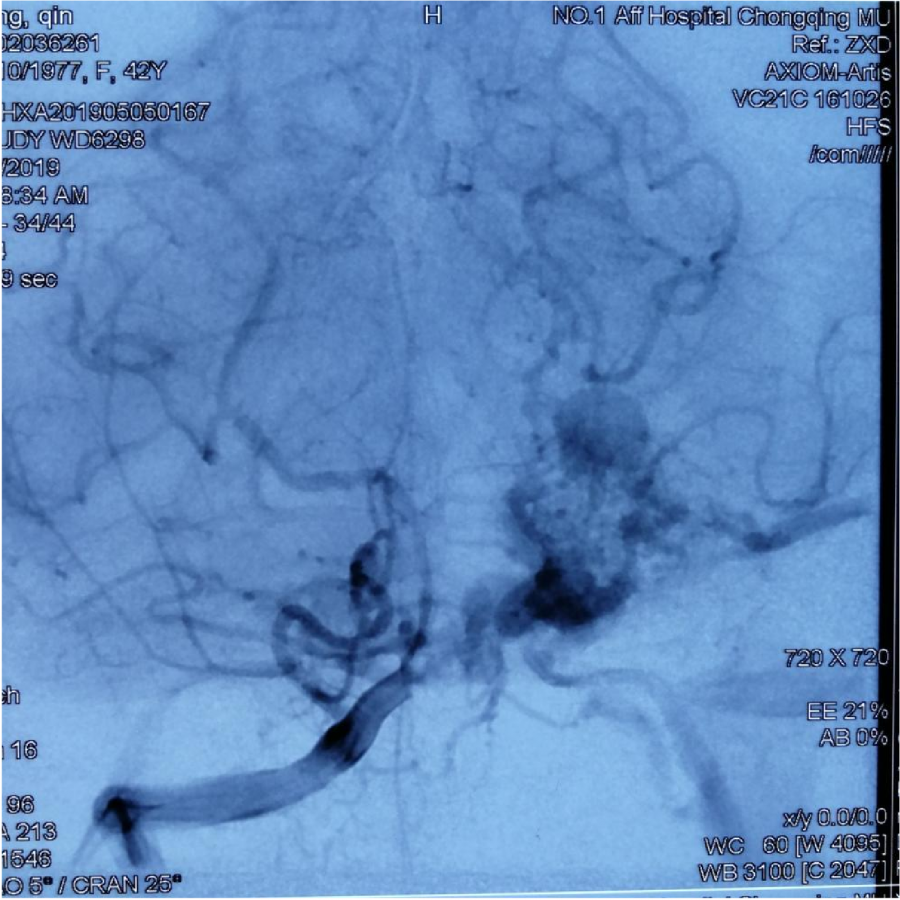

第⼀次DSA显⽰PICA供⾎

引流⾄⼄状窦

小脑后下动脉、小脑前下动脉参与供⾎

颈外动脉造影显⽰枕动脉参与供⾎

本次⼊院⾏DSA检查:PICA供⾎区有畸形⾎管团,引流到横窦